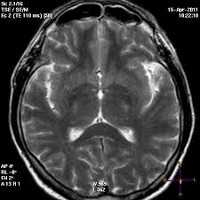

(а) МРТ, Т1-ВИ, аксиальный срез: у новорожденного с гипербилирубинемией, ступором, гипотонией и повышенной нервной возбудимостью определяется повышение интенсивности сигнала от бледных шаров и хвостов гиппокампов.

(б) МРТ, Т1-ВИ, аксиальный срез: у того же пациента отмечается двустороннее аномальное повышение интенсивности сигнала от гиппокампов и черной субстанции билатеральной. Кора больших полушарий и подлежащее белое вещество в норме. (а) МРТ, Т2-ВИ, аксиальный срез: у этого же ребенка в возрасте шести месяцев определяется двустороннее повышение интенсивности сигнала от бледных шаров и потеря их объема. Объем белого вещества больших полушарий несколько уменьшен.